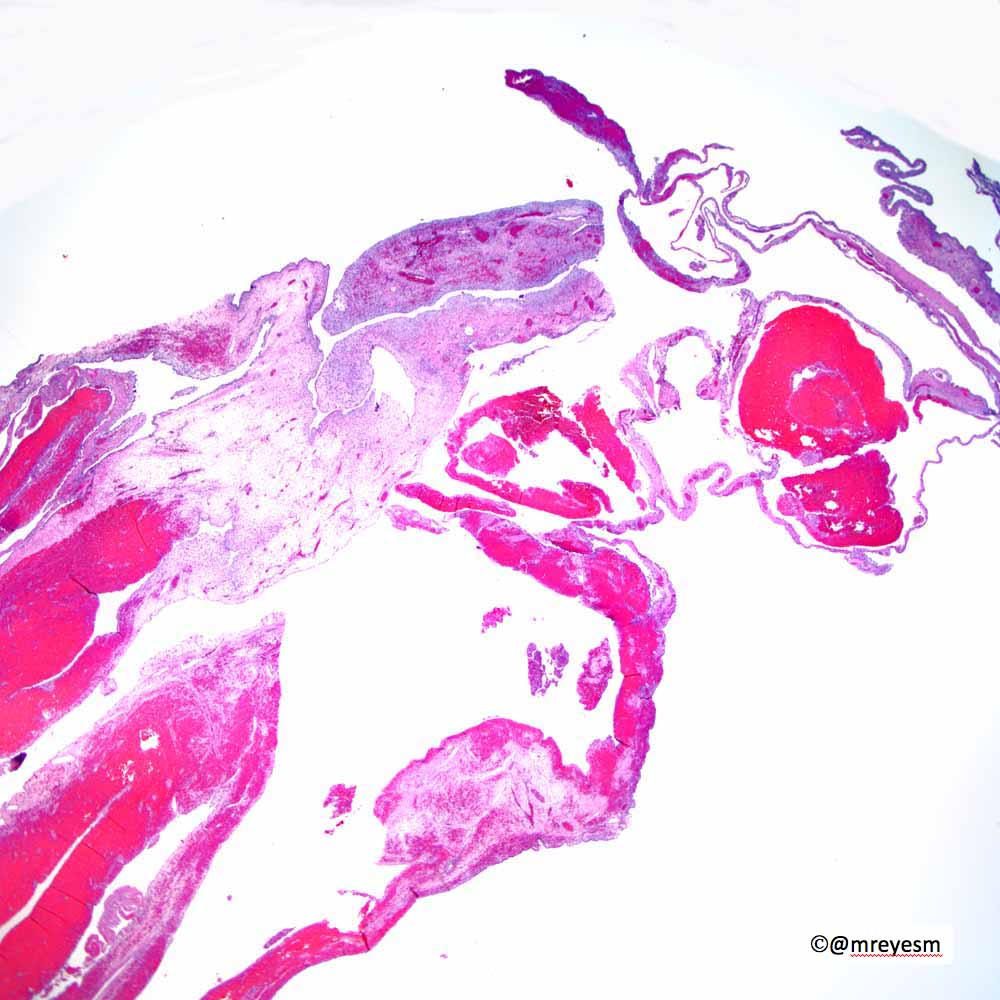

@thoracicpath

Charles Leduc, MD

4 years

Thanks to all who engaged! Although uncommon, chronic LCH can lead to severe secondary pulmonary HTN which is what we see here. A spectrum of arterial lesions, including plexiform, dilatation, and medial hypertrophy. Wishing the patient a new lease on life with new lungs!

!

Explants from woman in her mid 40s. Clinical history on req: pulmonary hypertension. IHC is CD1a. Unifying diagnosis?